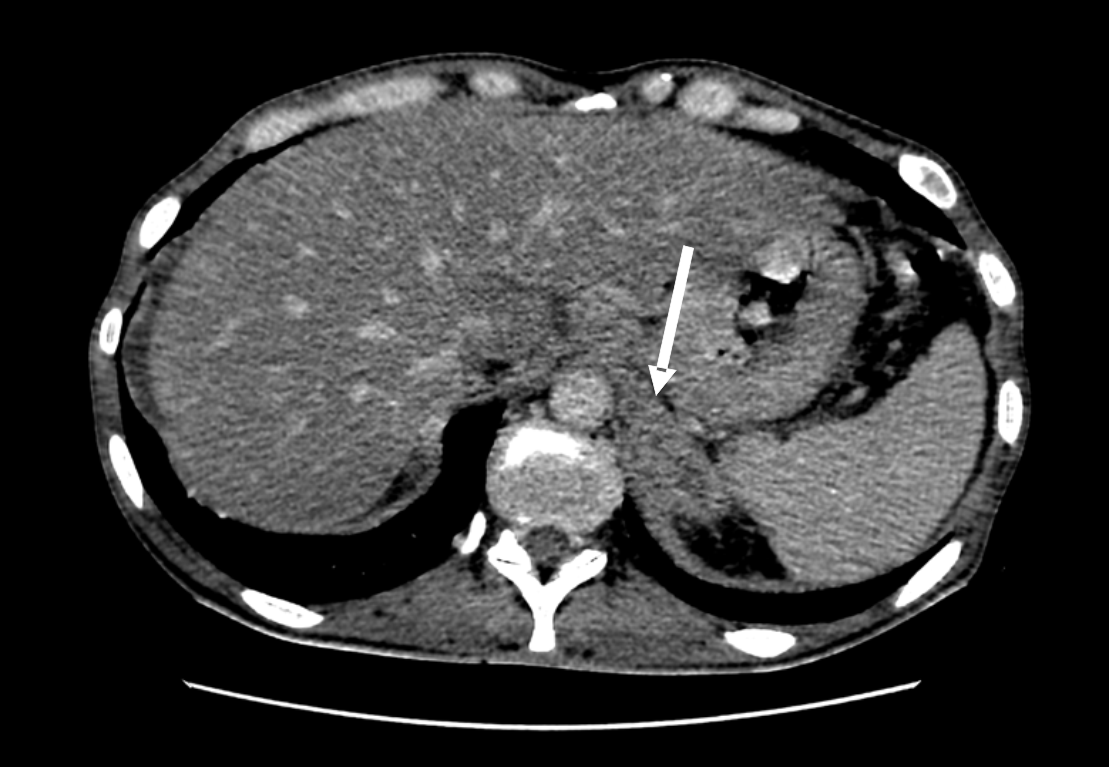

По данным компьютерной томографии (КТ) органов грудной клетки выявлены увеличенные до 16 мм лимфатические узлы метастатического характера. На КТ органов брюшной полости обнаружены образования по малой кривизне желудка (стенка неравномерно утолщена) и множественные вторично измененные лимфоузлы (парагастрально, в забрюшинном пространстве и брюшной полости), а также образование левого надпочечника до 36 мм по короткой оси (рис. 1), вторичного характера, в малом тазу определяется жидкость, метастаз в яичники (рис. 2), асцит, лимфаденопатия, жировой гепатоз. При выполнении магнитно-резонансной томографии (МРТ) выявлена картина единичных очагов сосудистого генеза белого вещества больших полушарий головного мозга, структурная неоднородность гипофиза в левых отделах.

Риc. 1. КТ органов брюшной полости. Метастаз в левый надпочечник (указан стрелкой)